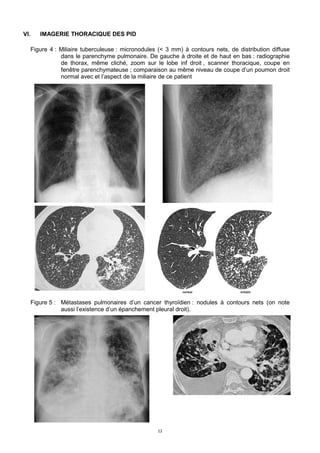

Figure 13 : Histiocytose langerhansienne se traduisant par l’association de kystes, de nodules

pleins, des nodules « troués » et de lésions de destruction parenchymateuse de forme

aléatoire émanant de la confluence de kystes, épargnant l’extrême base du poumon.

Figure 14 : lesions microkystiques décrivant un aspect en « rayon de miel » au cours d’une

fibrose pulmonaire idiopathique

Figure 15 : Bronchectasies « par traction » au cours d’une fibrose pulmonaire idiopathique